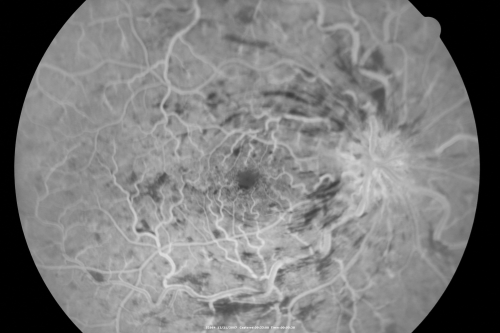

49-year-old woman has central retinal vein occlusion right eye with fluctuating vision for a few month now with OD 20/100. IOP: OD 20

CRVO and CME treated with intravitreal Kenalog 49 Year Old Woman